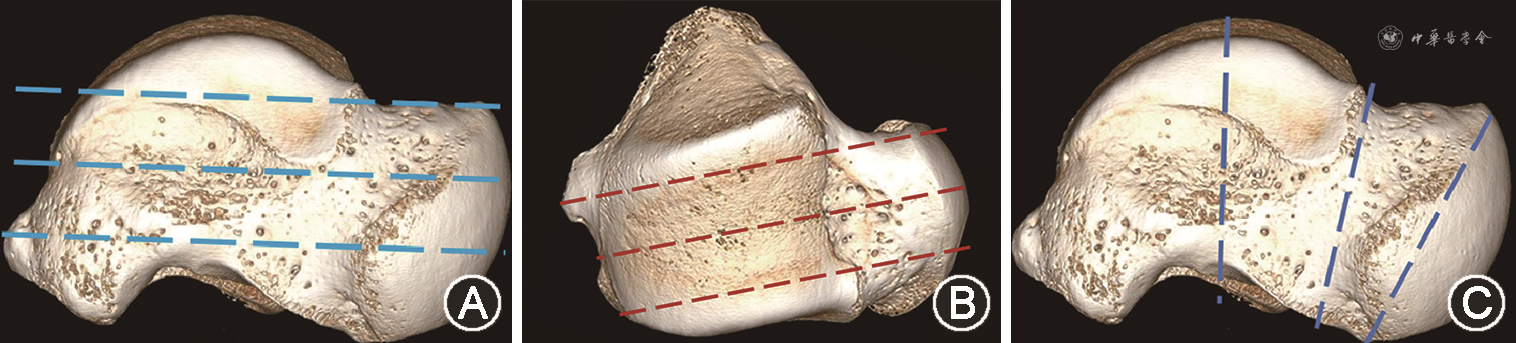

为研究距骨内骨小梁结构,使用硬组织切片机(德国艾卡特公司E300CP型)分别在冠状面、矢状面及水平面将距骨切成2 mm厚的薄骨片,随后使用超高分辨X线成像系统(美国Faxitron公司)对切片进行扫描,扫描电压10~100 kV,电流0.3 mA(图1),对所得冠状位、矢状位及水平位X线片距骨头、颈、体小梁走行、疏密、结构进行大体描述。在进行组织切片前,对全部距骨使用德国Siemens公司InveonTM系统的Micro-CT机器进行扫描并三维重建,扫描电压80 kV,电流500 μA,扫描分辨率为36.12 μm(中分辨率),分别计算距骨头、颈、体的骨体积分数(BV/TV,%)、骨表面积分数(BS/BV,mm-1)、骨小梁厚度(Tb.Th,μm)、骨小梁数目(Tb.N,mm-1)、骨小梁间距(Tb.Sp,μm)及骨小梁模式因子(TPF,mm-1),分别对相同侧别不同部位以及相同部位不同侧别的各项参数的差异进行比较(图2)。

在距骨上部的水平面切片中,距骨切面中部骨小梁主要沿距骨的长轴前后方向排列延伸,同时两侧小梁垂直起始于胫距及腓距关节面,向中部延长轴汇聚,体部小梁排列较颈部较为致密。在颈部区域小梁逐渐变得稀疏且较体部小梁更粗;在头部,小梁方向发生偏转,似板状重叠排列。在水平面切片中部,骨小梁头体密颈疏的特点越发明显,且头体部小梁交织密集,颈部虽较疏松,但颈中部连接头体的小梁明显较距骨颈沿皮质周围的小梁更粗密。在下部,距骨体部小梁呈网格状相互交织,无明显走向;颈部小梁较上中部更为稀疏,使得颈中部小梁粗密程度更为明显,头部小梁与上中部一样保持板状密集,如图3。